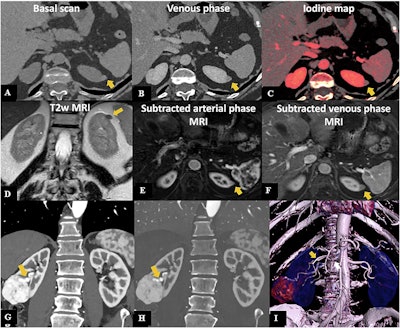

PCCT in renal cancer. A 57-year-old woman undergoing PCCT. Axial pre-contrast (A) and venous phase (B) scans show a small exophytic nodule of the superior pole of the left kidney (11 mm), slightly hyperdense in both phases, with mild iodine uptake at the iodine map (C), suggestive of a small papillary neoplasia rather than a hemorrhagic cyst. MRI confirmed the presence of a small left kidney nodule, hypointense in the T2w image (D), characterized by mild enhancement in the arterial phase (E), with minimal washout in the venous phase (F), thus confirming PCCT suspicion. PCCT in kidney tumor surgery planning: coronal angiographic CT scan showing an exophytic heterogeneous lesion in the mid-lower right kidney (G), 5 cm in diameter, with a well-defined hypertrophic vascular pole, further highlighted on the iodine map (H). 3D reconstruction shows a double right renal artery; the lesion is supplied by the more caudal branch (white arrow in I).Bruno, Palmisano et al; Insights into Imaging